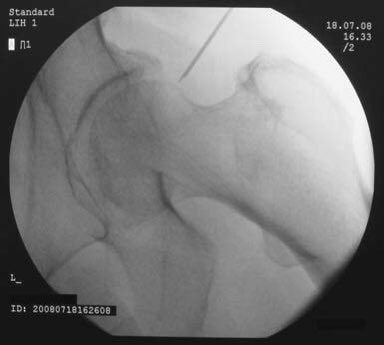

وتبدأ عملية الخشونة والاحتكاك عندما تبدأ طبقة الغضروف المبطن بالتآكل عندها تبدأ عملية التهاب كبسولة المفصل وتكون التشوهات المصاحبة ويبدأ تضيق المفصل في الاشاعة السينية ونلاحظ احتكاك عظمة الفخذ بعظمة الحق

في بعض الحالات نلجأ الى بعض الإبر المسكنة في المفصل لتساعدنا بشكل أدق عن مصدر الألم